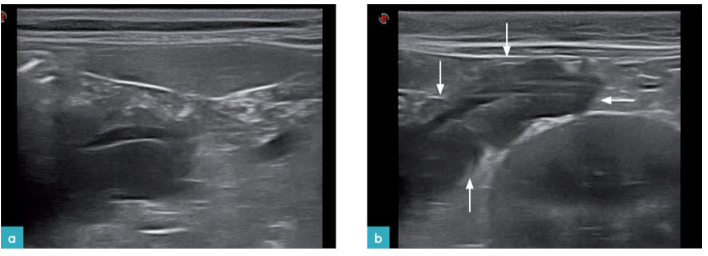

胰腺水肿

胰腺水肿表现为胰腺增厚,实质内有多条低回声或无回声条带。胰腺水肿可能与胰腺炎有关,也可能与低白蛋白血症,门静脉高压及全身性血管炎有关。